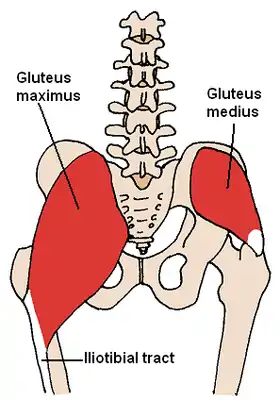

The gluteus medius and nearby muscles. | |

Position of gluteus medius muscle (shown in red). Hip bone is shown in semi-transparent. Structures surrounding right hip-joint.